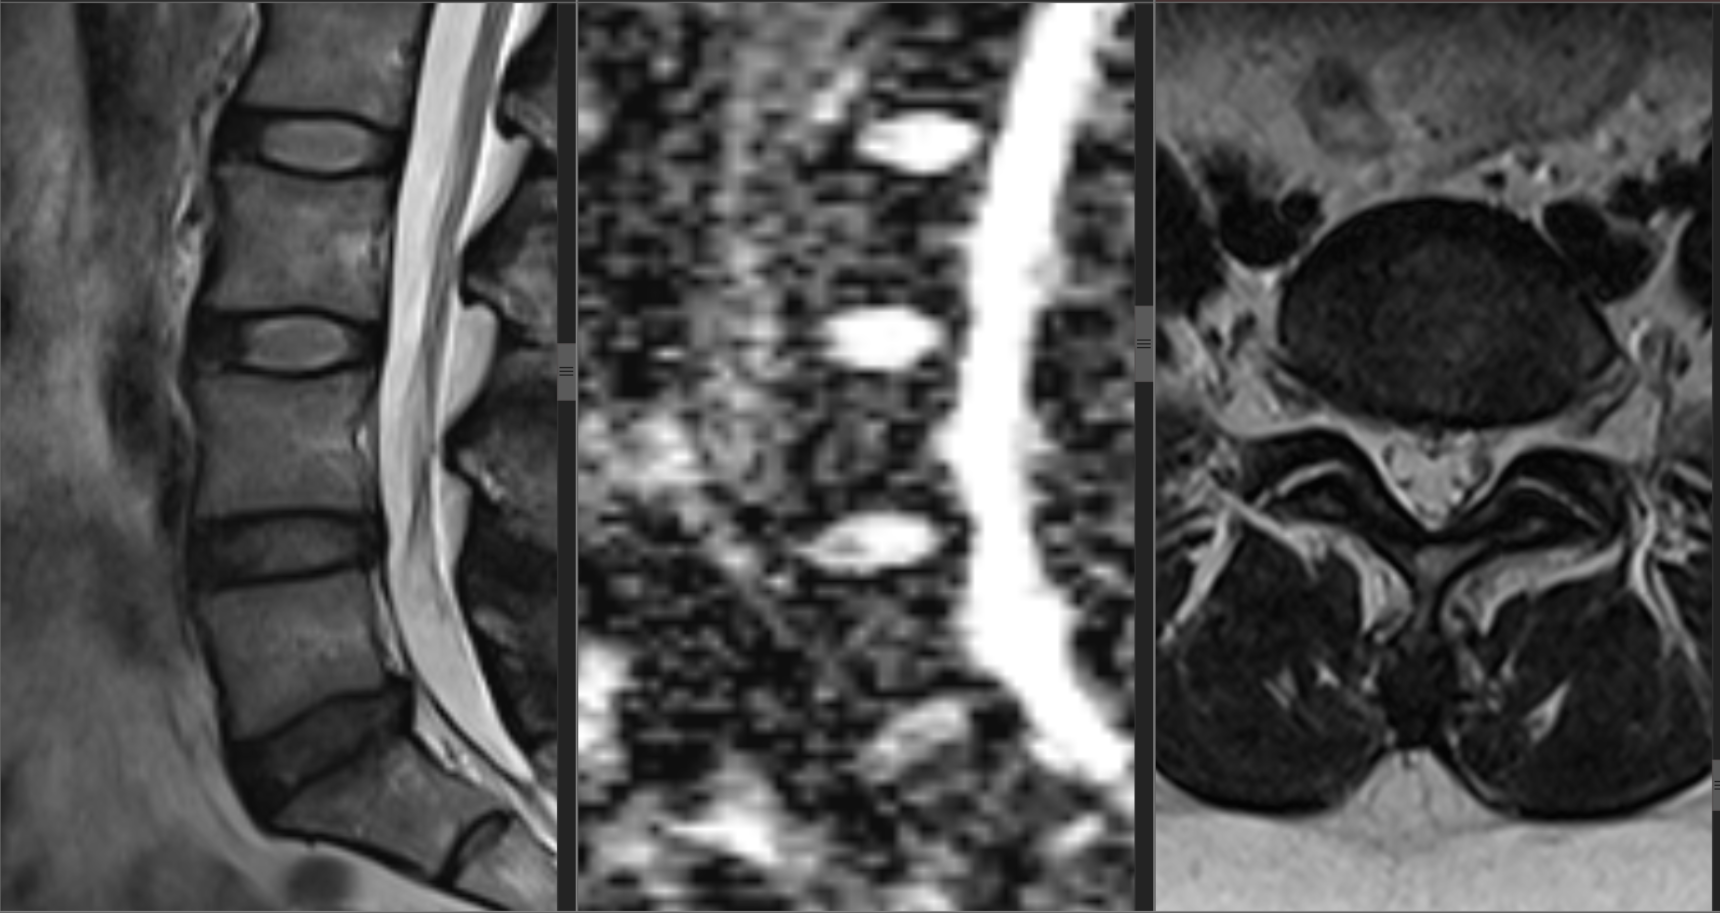

Клинический пример. Больная Л., 42 лет (24.02.1981 г.р.) в 2023 г., поступила в нейрохирургическое отделение Иркутского научного центра хирургии и травматологии с жалобами на боли в поясничном отделе позвоночника на протяжении 14 лет. Свое состояние связывает с физическими нагрузками на позвоночник, переохлаждением. Боли в правой ноге появились с конца января 2023 года. Постепенно боли в пояснице, правой ноге становились более интенсивными, и практически постоянными. Консервативное лечение у невролога по месту жительства с временным эффектом. Выполнила МРТ поясничного отдела позвоночника. МРТ пояснично-крестцового отдела от 22.06.23 г. (рис.3).

В неврологическом статусе: вертеброгенная люмбоишиалгия справа; положительный симптом Лассега справа 800 (+), прямой; умеренный стойкий болевой и мышечно-тонический синдромы.

Клинический диагноз: Дорсопатия. Дегенеративно-дистрофические изменения поясничного отдела позвоночника. Спондилоартроз LIV-LV. Протрузия на уровне LIV-LV. Люмбоишиалгии справа. Умеренный болевой и мышечно-тонический синдром. (Код МКБ М 51.1).

24.10.2023 г. пациентке Л. была проведена магнитно-резонансная томография в режиме диффузно-взвешенного изображения; были определены коэффициенты диффузии пульпозного ядра межпозвонкового диска в сагиттальной и парасагитальных плоскостях для межпозвонковых дисков на уровне позвоночно-двигательных сегментов (ПДС): LII/LIII, LIII/LIV, LIV/LV, LV/SI и коэффициент диффузии ликвора просвета дурального мешка, свободного от невральных структур.

а                                         б                                                   в

Рис. 3. МРТ изображение поясничного отдела позвоночника больной Л.: а) Т2 взвешенное изображение с оценкой изменений по Pfirrmann в сагиттальной плоскости; б) диффузно-взвешенное изображение с измеренными показателями ИКД дисков и ликвора в сагиттальной плоскости; в) аксиальный срез исследуемой зоны. Дегенеративно-дистрофические изменения поясничного отдела позвоночника. Спондилоартроз LIV-LV. Протрузия на уровне LIV-LV. Спондилез.

Fig. 3. MRI image of the lumbar spine of patient L.: a) T2 weighted image with Pfirrmann assessment of changes in the sagittal plane; b) diffusely weighted image with measured values of ICD discs and cerebrospinal fluid in the sagittal plane; c) axial section of the studied area. Degenerative-dystrophic changes of the lumbar spine. Spondyloarthritis LIV-LV. Protrusion at the LIV-LV level. Spondylosis.

Значения ИКД рассчитаны автоматически с помощью программного обеспечения и отображены в виде параметрической карты, на которой и были выделены области интереса: ИКД - ср. диск; ИКД ликвор. Полученные показатели представлены в таблице 2.

Были установлены величины коэффициентов дегенерации межпозвонковых дисков для исследованных уровней ПДС:

Х LII/LIII = 1449,50/2364,75=0,61

Х LIII/LIV = 1601,71/2364,75=0,68

Х LIV/LV = 1330,40/2364,75=0,56

Х LV/SI = 804/2364,75=0,34

Из сравнения величин Х с показателями степени дегенерации по Pfirrmann установлено значимое расхождение цифровых показателей для межпозвонковых дисков LII/LIII, LIII/LIV, следовательно, предлагаемый и рассчитанный коэффициент диффузии более точно и специфично отразил произошедшие дегенеративные изменения у пациентки.

Клинический пример пациентки Л. наглядно демонстрирует практическую ценность и повышенную чувствительность предложенного метода. При стандартной оценке по Pfirrmann диски на уровнях LII/LIII и LIII/LIV были отнесены к одинаковой II стадии дегенерации. Однако расчет коэффициента X выявил между ними существенную количественную разницу 0,61 и 0,68. Это различие, не уловимое при визуальном анализе, указывает на то, что дегенеративные изменения в диске LII/LIII являются более выраженными. Данный случай иллюстрирует, что коэффициент X обеспечивает более тонкую и объективную градацию состояния дисков. Это имеет прямое клиническое значение для стратификации пациентов, планирования тактики лечения (например, выбора мишени для интервенционных методов воздействия) и для динамического наблюдения. Количественный характер метода позволяет фиксировать незначительные изменения в состоянии диска еще до того, как они приведут к смене визуальной стадии по Pfirrmann. Для пациентов с длительным болевым синдромом, как в представленном случае, это открывает возможности для более точной диагностики и, как следствие, для более целенаправленного и эффективного лечения.